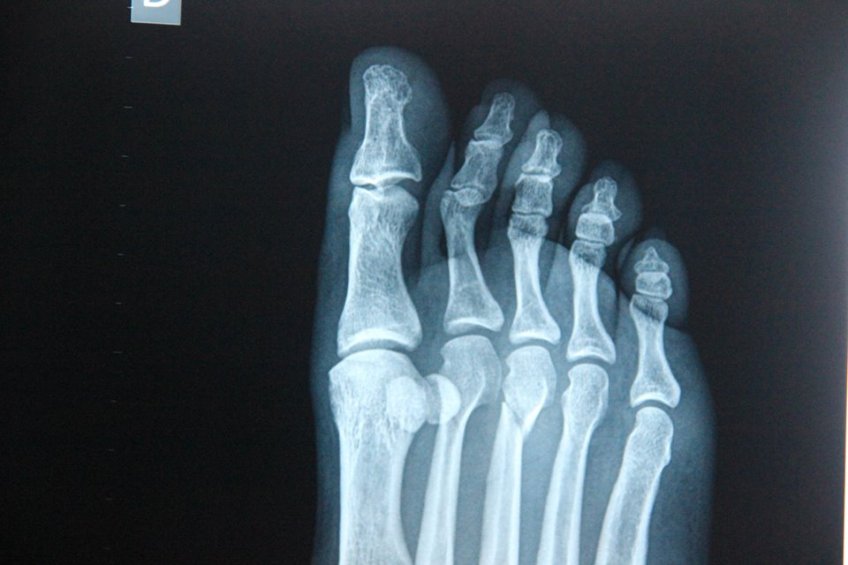

whatsnext2 Published February 6, 2015 at 960 × 640 in whatsnext2 aside from numbers two and three, a perfectly good looking foot